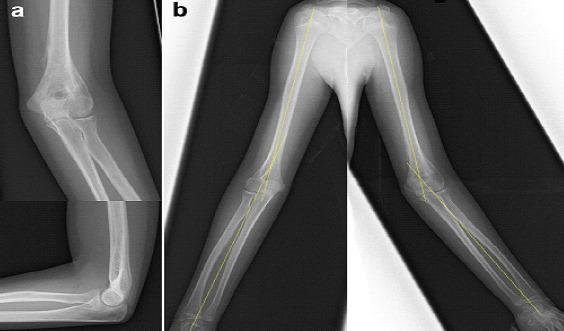

A 10-year-old girl had left-sided cubitus valgus deformity with persistent UN palsy 4 months after open reduction and internal fixation (ORIF) at another hospital. Half a year after the initial operation, corrective osteotomy of the distal humerus with neurolysis and subcutaneous anterior transposition of the UN were performed. She showed excellent recovery 14-month postoperatively and reported restored motor and sensory function with symmetrical elbow appearance.

一名10岁女孩在另一家医院接受切开复位内固定(ORIF)术后4个月,出现左侧肘外翻畸形且UN麻痹持续存在。初次手术后半年,对其进行了肱骨远端截骨矫形、神经松解及UN皮下前移术。术后14个月,她恢复良好,运动和感觉功能恢复,肘部外观对称。